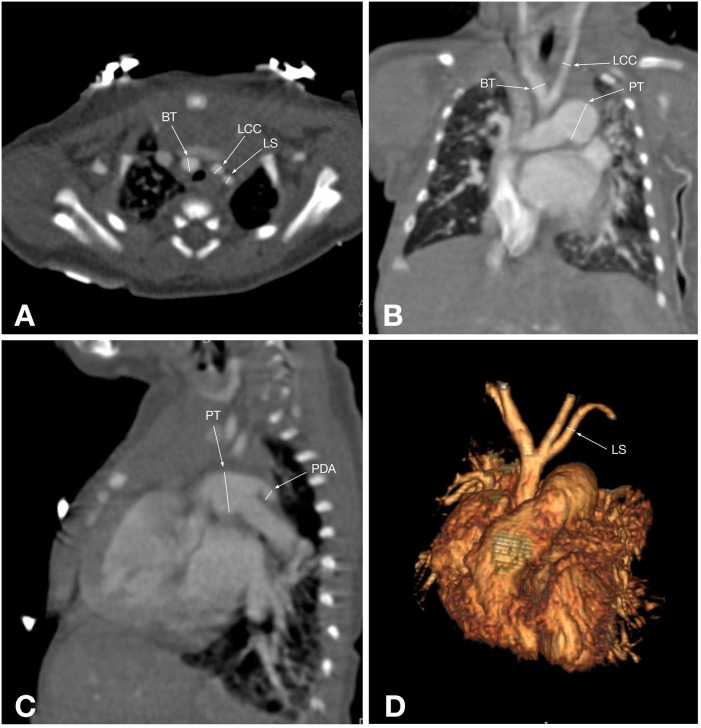

主动脉弓中断(IAA)是一种罕见的先天性心血管异常,其特征是升降主动脉之间缺乏连续性,通常伴有先天性心脏缺陷,如室间隔缺损和动脉导管未闭。准确的术前影像对手术计划和患者管理至关重要。本研究旨在比较超声心动图和计算机断层血管造影(CTA)在评估IAA患者胸部表现方面的诊断准确性。对2020年9月至2023年1月期间在哈萨克斯坦阿斯塔纳大学医学中心心脏中心诊断为IAA的58例患者(中位年龄:18天)进行了回顾性分析。常规超声心动图和多层CTA采用标准化方案。计算敏感性、特异性和其他诊断性能指标。采用McNemar和Wilcoxon有符号秩检验进行统计学比较,p p p = 0.09)。IAA主要为A型(48.3%)和B型(46.6%),34.5%的患者发现升主动脉发育不全。超声心动图仍然是IAA的一种实用的初始成像方式,具有便携性和成本效益。然而,CTA显示出优越的诊断准确性和解剖分辨率,使其成为详细的术前评估和手术计划的首选工具。未来有更大的队列和其他方式的研究可以进一步完善IAA的诊断策略。

Interrupted aortic arch (IAA) is a rare congenital cardiovascular anomaly characterized by the absence of continuity between the ascending and descending aorta, often accompanied by congenital heart defects such as ventricular septal defects and patent ductus arteriosus. Accurate preoperative imaging is essential for surgical planning and patient management. This study aimed to compare the diagnostic accuracy of echocardiography and computed tomography angiography (CTA) in evaluating thoracic findings in patients with IAA. A retrospective analysis was conducted on 58 patients (median age: 18 days) diagnosed with IAA between September 2020 and January 2023 at the Heart Center, University Medical Center, Astana, Kazakhstan. Conventional echocardiography and multislice CTA were performed using standardized protocols. Sensitivity, specificity, and other diagnostic performance metrics were calculated. Statistical comparisons were made using McNemar's and Wilcoxon signed-rank tests, with p < 0.05 considered significant. Echocardiography correctly identified 91.4% of IAA cases, while CTA achieved 100% sensitivity and specificity. McNemar's test revealed a significant difference in diagnostic performance favoring CTA (p < 0.05). Measurements of the ascending aorta diameter showed no statistically significant difference between the two modalities (p = 0.09). IAA was predominantly type A (48.3%) and type B (46.6%), with hypoplastic ascending aorta identified in 34.5% of patients. Echocardiography remains a practical initial imaging modality for IAA, offering portability and cost-effectiveness. However, CTA demonstrated superior diagnostic accuracy and anatomical resolution, making it the preferred tool for detailed preoperative evaluation and surgical planning. Future studies with larger cohorts and additional modalities could further refine diagnostic strategies for IAA.